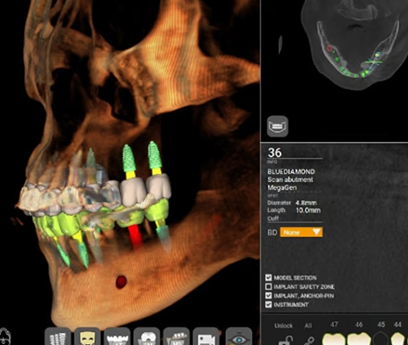

В нашей клинике используется цифровая система планирования, что позволяет точно спланировать место установки каждого импланта, минимизировать хирургическое вмешательство и сразу же установить индивидуальные протезы.

Сложные случаи: полная имплантация